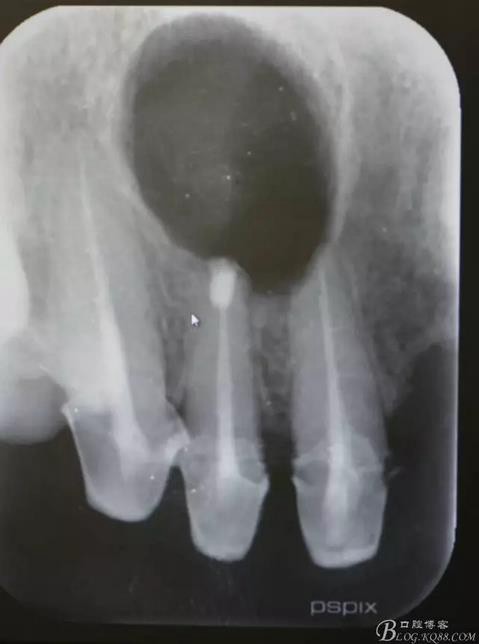

患者、王xx、女、56歲。主訴:右側上顎部反復腫痛兩年。??茩z查:上半口烤瓷橋修復,12腭側隆起,捫診有輕微觸痛。X光:12根尖有圓形規(guī)則陰影,范圍月、約1.0x1.2cm,邊界清晰,11、12根管治療不完善。診斷:12根尖囊腫。治療計劃:1.行11、12根管治療術。2.擇期行根尖手術?;颊咄庵委煼桨?,簽知情同意書。

圖1.術前的根尖片影像檢查:11、12根管治療不完善

圖20.術后根尖片影像檢查